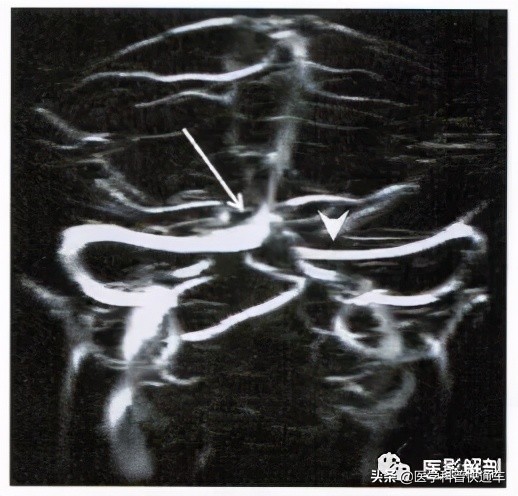

图2 右侧横窦及乙状窦较粗大

颅内静脉窦TOF法MRV检査。MRV重组图显示右侧横窦及乙状窦较左侧粗大接近1倍。右侧横窦(箭)与上矢状窦相连,左侧横窦(箭头)及乙状窦显影纤细,左右横窦之间无连接。

颅内静脉窦的发育程度在个体间差异较大。最常见的表现形式是成对的静脉窦左右两侧粗细不对称,尤其是双侧横窦及乙状窦。优势侧静脉窦往往校为粗大,且以右侧多见( 图2 )。